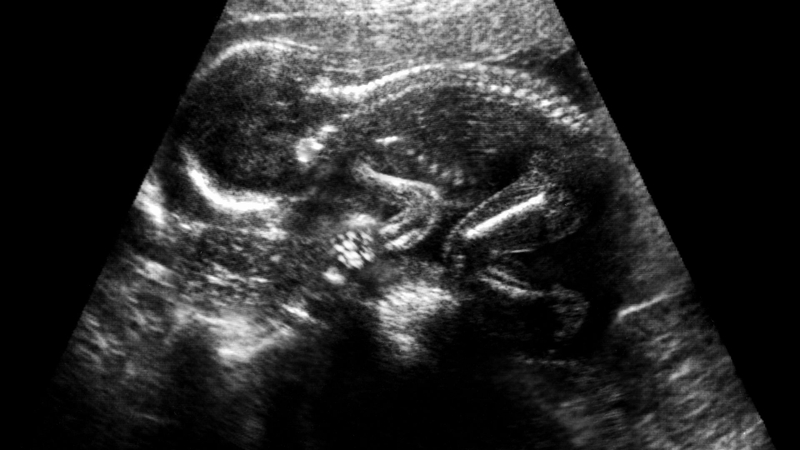

Ruột tăng âm ở thai nhi cần phải làm gì? 4

Cần làm thêm các xét nghiệm khác khi phát hiện ruột tăng âm